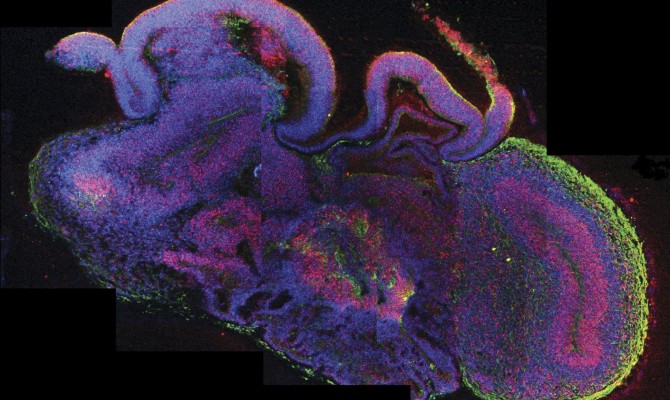

Ученые вырастили мини-мозг в лаборатории

Фото: Reuters